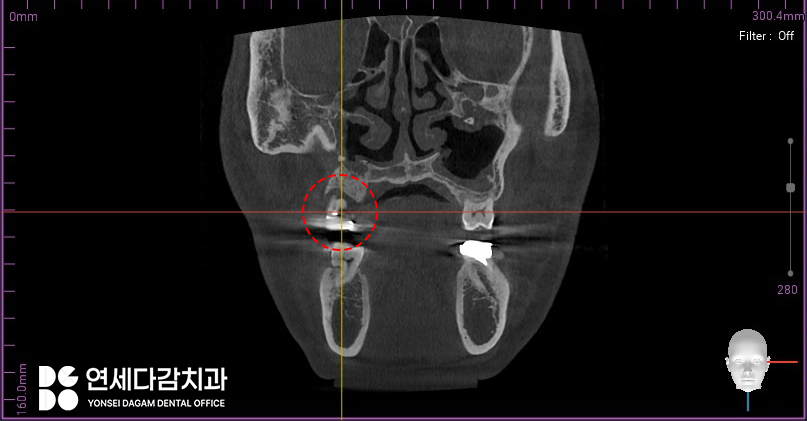

Caldwell-Luc Operation을

받은 환자들의 경우,

상악동 골벽에 결손이 발생한다는

전형적인 특징이 있습니다.

의도적으로 만든 공간이

다 닫히지 않고 일부 골결손 상태로

남아있는 경우가 많기 때문입니다.

이러한 골벽이 상실된 채로

오래 지내다 보면

임플란트 식립에 필요한 뼈가 부족하여

치료가 까다로워질 수밖에 없습니다.

따라서 이러 경우 CT 분석을 통해

사용할 수 있는 뼈를 미리 정확히 확인하고,

송파구 치과 에서는 이렇게 다양한 각도로

3차원적으로 구조를 살펴보며

염증의 범위를 살펴봅니다.

또한 결손 부위를 피해 가능한

건강한 골조직에 위치하도록

신중하게 각도와 깊이를 계획하고,